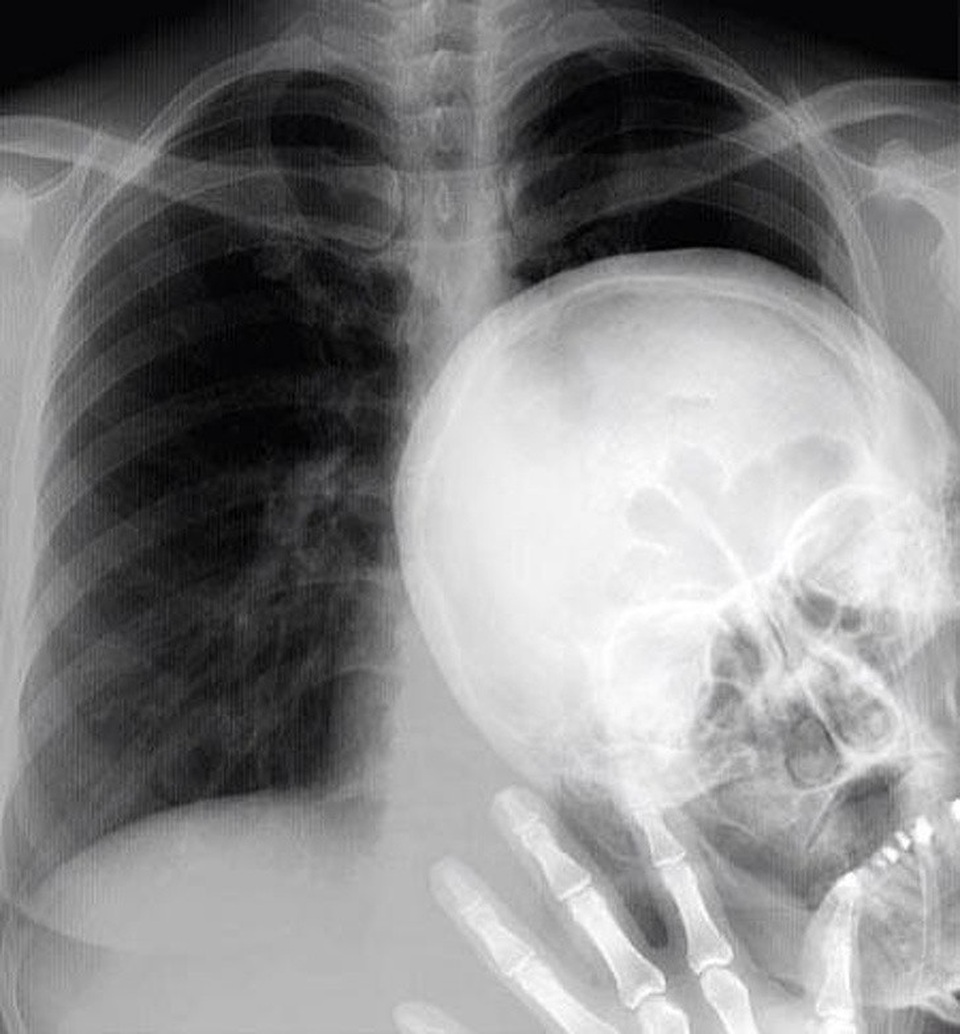

(Dân trí) - Hình ảnh chụp X-quang của những chủ thể đặc biệt như: một chú mèo đang mang thai, bộ phận cơ thể bị dị tật bẩm sinh hay thậm chí là bụng của cô bé nuốt nhầm chiếc bấm móng, được tổng hợp dưới đây, sẽ giúp bạn như bước vào một thế giới mà mình chưa từng biết!